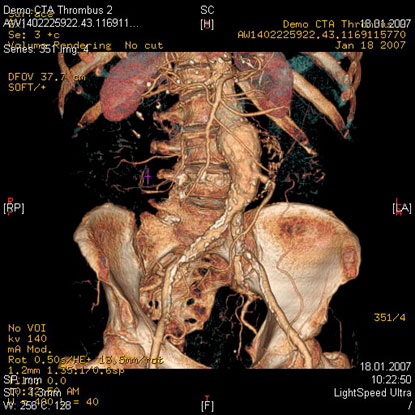

МСКТ высоко чувствительна в диагностике атеросклеротических кальцинированных, ,,мягких,, бляшек. В большинстве клиник метод МСКТ стал основным методом диагностики заболеваний сосудов сонных артерий, грудной, бюшной аорты, периферических пртерий.

- диагностика сосудистых заболеваний (аневризмы, стенозы, мальформации, аномалии развития)

- Выявление венозного тромбоза

Эмболии лкгочной артерии, источником которых обычно являются тромбы в венах таза и нижних конечностей являются грозным и относительно частым осложнением особенно у лежачих больных и после операции. Данные при рентгенографии неспецифичны. Без инфаркта может определяться приподнятие купола диафрагмы и сужение теней сосудов к периферии. Возможности МСКТ в диагностике ТЭЛА в ряде случаев позволяют отказаться от проведения инвазивной ангиографии.